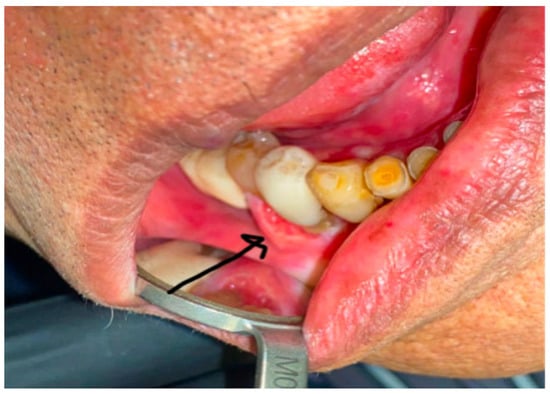

A 91-year-old female with minimal comorbidities presented for treatment of a gingival carcinoma. Upon examination, an approximately 3 cm × 2 cm exophytic, ulcerated, gingival mass was found invading into the cortical bone of the right mandible. A biopsy confirmed the presence of invasive squamous-cell carcinoma. There was clear clinical invasion of the mandibular alveolus in the vicinity of a prosthetic dental bridge (Figure 1). The patient did not display any cervical adenopathy, and her cranial nerve exam was normal. Laboratory evaluation revealed no signs of anemia or metastatic disease. Computed tomography imaging supported the diagnosis of carcinoma with mandibular invasion, past the cortex and into the marrow of the alveolus without evidence of regional or distal metastasis (Figure 2). Therefore, the patient was staged as a cT4aN0 squamous-cell carcinoma of the right mandible. We presented the patient with various treatment options, including curative surgical intervention that would require mandibular resection, reconstruction, selective neck dissection, and possible need for tracheostomy. Additionally, we discussed the possibility of curative intent, definitive, concurrent chemo-radiation. Though this is a less standard curative option with a lower potential cure rate, it was discussed as an option to avoid surgery. Finally, given the patient’s advanced age, we also discussed non-curative palliative treatment options, such as primary immunotherapy. We assessed the patient’s goals of care, and she emphasized the importance of maintaining quality of life, rather than quantity. She was referred to our geriatric oncology clinic for further discussion of goals of care and an assessment of life expectancy based upon age and comorbidity, aside from her oncologic prognosis. She also saw head and neck medical oncology, and she reiterated her goal of quality of life over long-term cure. Her CPS score was 85%.

An 82-year-old male with an ECOG classification of 0 presented for evaluation of a mild to moderately painful recurrent mandibular gingival carcinoma. He had previously been treated with a combination of surgery and radiation therapy for a cT2N0 squamous-cell carcinoma of the right mandible. Three years later, he presented with a recurrence in the right mandibular gingiva, specifically at the level of the premolars (Figure 5). A biopsy confirmed the recurrence as rT2N0 squamous-cell carcinoma. Pretreatment MRI revealed swelling in the right gingiva buccal region of the mandible (Figure 6a). Additionally, there was evidence of cortical erosion in the right mandibular premolar region, indicating superficial invasion of the recurrent malignancy. Notably, there was no cervical adenopathy.

Figure 5. Pretreatment photograph of patient #2: arrow points to exophytic gingival mass between the two right mandibular premolars in the site of biopsy-proven squamous-cell carcinoma.